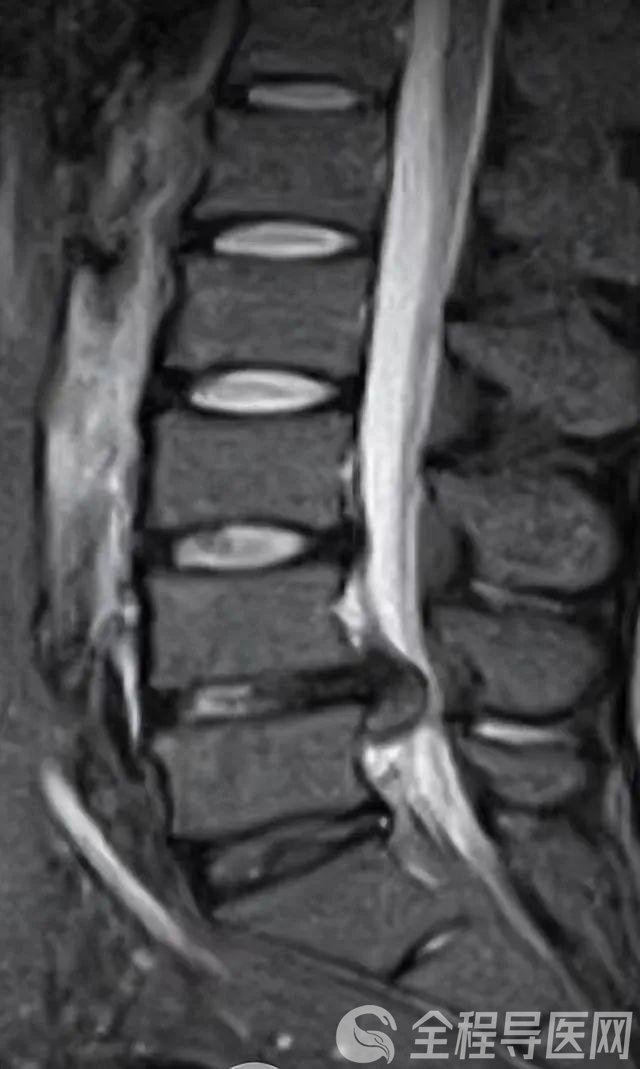

全程导医网 徐矿总医院频道:94岁的老太太突然腰疼到无法正常行走,家人急忙将其送到医院。经过细致检查虽然确诊是腰椎间盘突出,但是因为老人年事已高且有基础性疾病,医生不敢轻易手术,只能采取保守治疗。

近一个月来,她的病情逐渐加重,行走一二十米就不行了,同时伴有严重的双下肢麻木情况。最近一周甚至腰疼到无法行走,甚至出现小便困难、大便失禁,严重影响了日常生活。

接诊后,刘加元主任医师带领团队结合患者的病史、体征和影像学检查等,制定了详细手术方案。在排除手术禁忌症后,刘加元手术团队在局部麻醉下为患者实施了微创椎间孔镜手术。

术中取出大量导致压迫的病变增组织后,手术台上患者双大腿及小腿麻木症状明显缓解,手术切口仅有1厘米。手术耗时半小时,术中患者全程可以清醒地与医生进行交流。术后患者腰疼消失。手术当天下午,患者就可以下地活动。随后康复的过程中,其精神面貌越来越好,渐渐恢复了往日的“元气”。